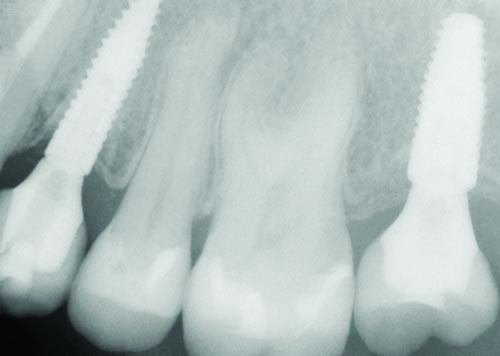

Fig. 32

Figs. 30–32: Two weeks later, the fourth appointment was reserved for restoration try-in and final impressions on the endosteal implants. It was during the fifth appointment, scheduled for two weeks later, that the implant-supported IPS E.max crown restorations were delivered, as well as the other definitive maxillary restorations, and any necessary adjustments made. These postoperative radiographs confirmed healing at the #3, #12 and #15 sites, which were all ultimately restored with Straumann implants, custom titanium abutments and IPS E.max crowns.